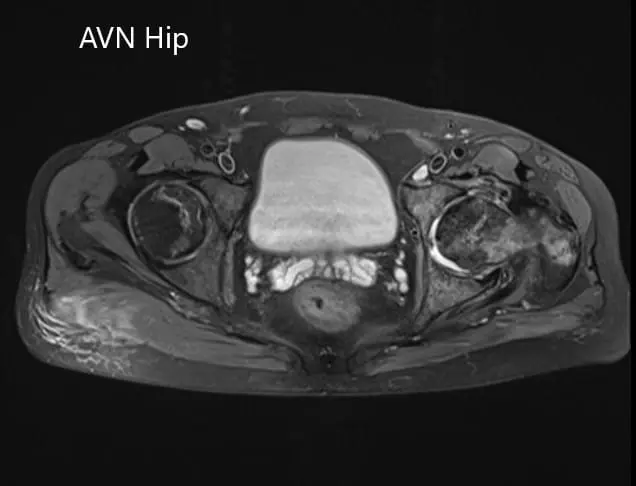

An MRI of the pelvis was obtained which suggested decreased signal intensity on both T1WI and T2WI suggesting sclerosis and periarticular edema. There was a collapse of the head of the femur. The features were suggestive of advanced avascular necrosis of the left hip joint.

Axial section of the T2WI of the pelvis